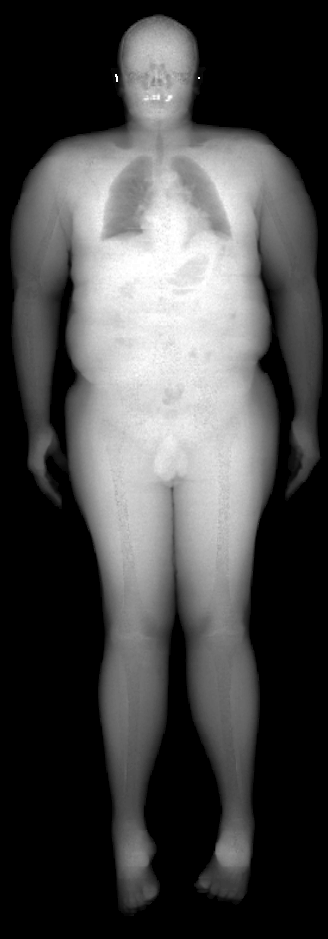

The key problem, however, is obtaining training data that simultaneously gives the inside and outside of the body in 3D. Most imaging technologies that simultaneously capture the inside and outside of the body use ionizing radiation, which is harmful to humans; e.g. Computed Tomography (CT) and X-rays. This means that such data is extremely limited, preventing learning-based methods. Our insight is to use dual-energy X-ray absorptiometry (DXA) data. DXA scans use low-dose X-rays to measure bone mineral density and body fat composition. The radiation level is so low that it is certified to be used on healthy patients for clinical studies, such as the UK Biobank [36]. In a DXA scan, two images are computed by combining two different energy levels: a soft-tissue image and a bone image (Fig. 2). In the silhouette of the body can clearly be seen, whereas reveals the structure and shape of the bones.

From the input images (, ), we compute the corresponding skin and skeleton segmentation masks (, ). For the skin mask , we threshold . As some small artifacts remain, mainly due to pixels in the lungs with low intensity values, we detect the closed contours on the image and fill in small areas. In Fig. 2 we show pairs of input and the obtained mask .